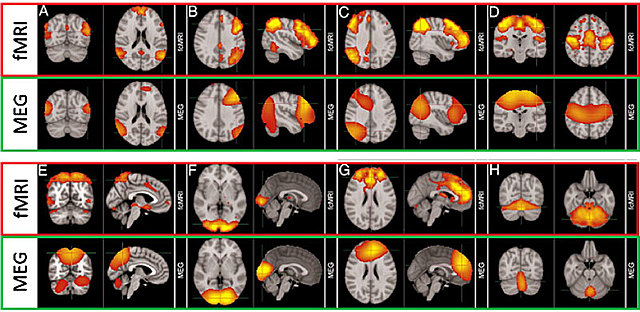

• Magnetoencefalografía (MEG)

Magnetoencefalografía (MEG)

Es una técnica usada para ver la actividad del cerebro vista a través de imágenes por resonancia magnética. El cual permite ver a detalle registros funcionales del encéfalo. (Carlson,20149